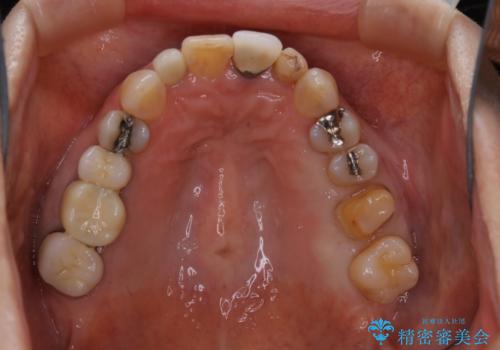

大きな詰め物を被せ物に変えて、歯の破折リスクを減らす

- 以前に異なる種類の材料で継ぎ接ぎ状態で修復されており、隙間のところから虫歯が再発していました。歯の手前側と後方及び内側に亀裂も入っていたため、将来的な虫歯再発のリスク及び歯の破折リスクを最小限にとどめるよう、被せものにて治療を行いました。

- 仮歯1万円・フルジルコニアクラウン7万円(税別)費用は治療当時の料金となります